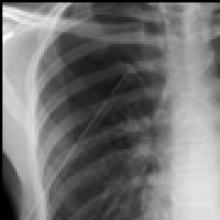

The chest tubes are maintained on suction for the day of the operation and then placed to water seal (Figure 6). Often, a small apical pneumothorax is seen which is usually of no significance and resolves over the next 2 to 4 weeks. Chest tube drainage can be high for the first 48 hours, after which a marked decrease is seen. If an air leak persists for more than 3 days, one of the tubes is left in the chest and the patient is discharged with a pneumostat device (Heimlich valve) or a minipleurevac if the chest tube drainage is more than 30cc/24 hours (Figure 7).

| Figure 6: Postoperative chest x-ray after blebectomy and pleurectomy. | Figure 7: Minipleurevac. |